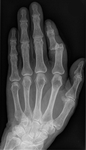

Dislocated distal phalanx, index finger, left hand

Bobjgalindo, CC BY-SA 4.0, via Wikimedia Commons